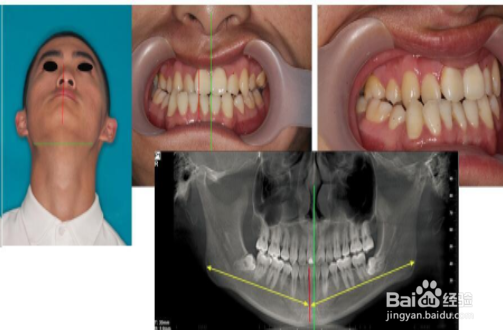

1、你自己对着镜子照下,看下自己牙齿咬合尺子 是否面部2测水平型,表现为颏部偏斜,无明显垂直向不对称,对侧前牙区反合或对侧磨牙舌倾。

4、如果长时间单侧咀嚼,现在一侧弹响 ,感觉张嘴时弹响的那一侧多出个圆的骨头鼓出来,另一侧没有。脸有偏斜,摸着两边骨头不一样长。